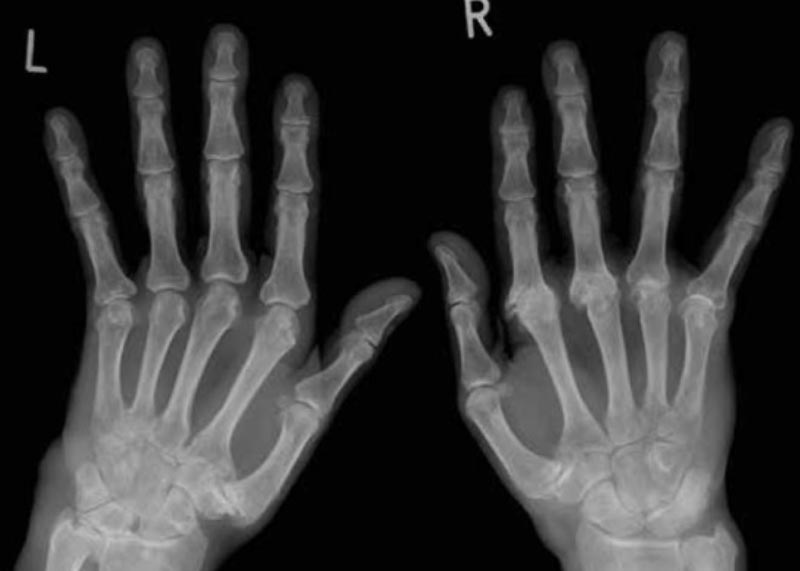

Um die Diagnose rheumatische Erkrankungen zu stellen, werden weitere Untersuchungen wie Ultraschall, Röntgen und MRT durchgeführt, welche beispielsweise Schäden an Knochen, Gelenken oder Sehnen feststellen können. Gelenkentzündungen oder auffällige Werte, die nur im Bluttest gefunden werden, haben nur begrenzten Nutzen bei der Diagnose einer rheumatischen Arthritis. Wenn aber mehrere Anzeichen gleichzeitig auftreten, ist die Wahrscheinlichkeit höher, dass Rheuma vorliegt.